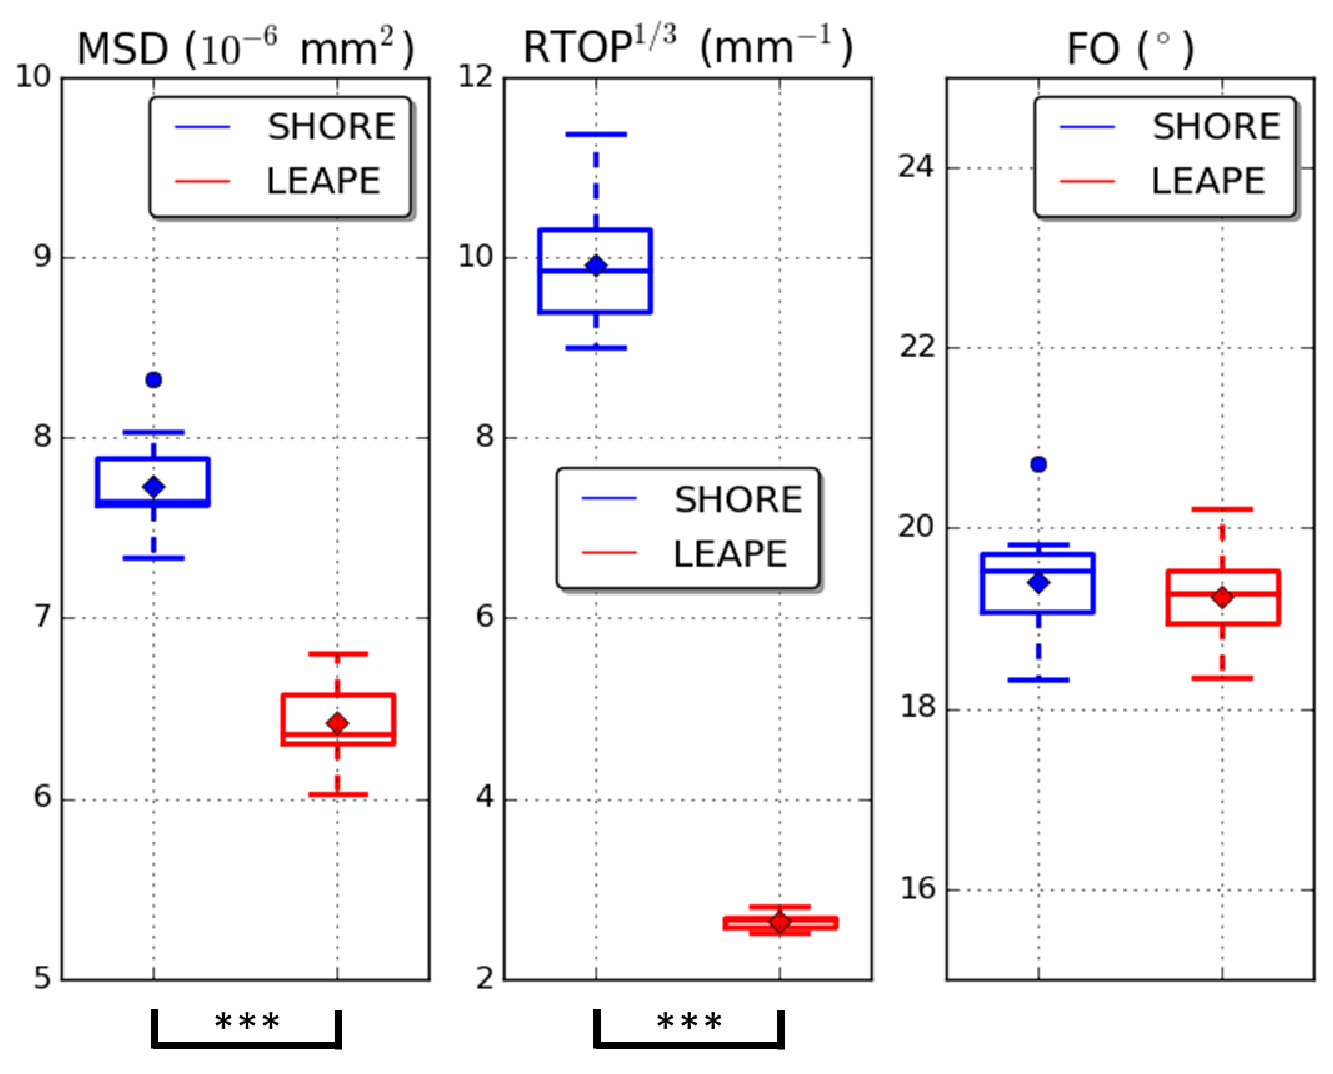

First, we evaluated the EAP estimation by examining the scalar features: MSD and RTOP. The LEAPE results on a representative subject are shown and compared with the gold standard and the results obtained by the conventional SHORE method [8] in a coronal slice in Fig. 3. Note that here for each MSD or map, the color map is the same for the three columns. The LEAPE results resemble the gold standard. The RTOP result of SHORE is remarkably biased with the smaller set of diffusion gradients. Then, we computed the average disagreement in the brain between the estimates and gold standard for the ten subjects, which is shown in the boxplots in Fig. 4. For both MSD and , the LEAPE errors are smaller than those of SHORE, and the differences are highly significant () using a paired Student’s -test.

Next, we evaluated the FOs extracted from the EAP. A qualitative comparison is made in Fig. 5, where we focus on a region where the corpus callosum (CC) and superior longitudinal fasciculus (SLF) cross. We can see that the LEAPE result resembles the gold standard, and LEAPE better resolves crossing FOs and produces smoother FOs than SHORE. The LEAPE FOs are even smoother than the gold standard in some cases. We also computed the average FO disagreement with the gold standard in the white matter for SHORE and LEAPE (see Fig. 4). Note that if the second MLP in LEAPE is not used for training, the FO errors range from to (not shown in Fig. 4), and for every subject the errors are higher () than those of SHORE or LEAPE. This indicates the benefit of adding the second MLP. Compared with SHORE, the mean and median of the disagreement of LEAPE are smaller. The difference of disagreement between SHORE and LEAPE is small. This is possibly because for the less complicated FO configurations (for example, noncrossing FOs), which occupy a large proportion of the white matter volume, both SHORE and LEAPE are able to produce good results with 60 diffusion gradients, and the difference like the one shown in Fig. 5 is present at regions with more complex FO configurations.